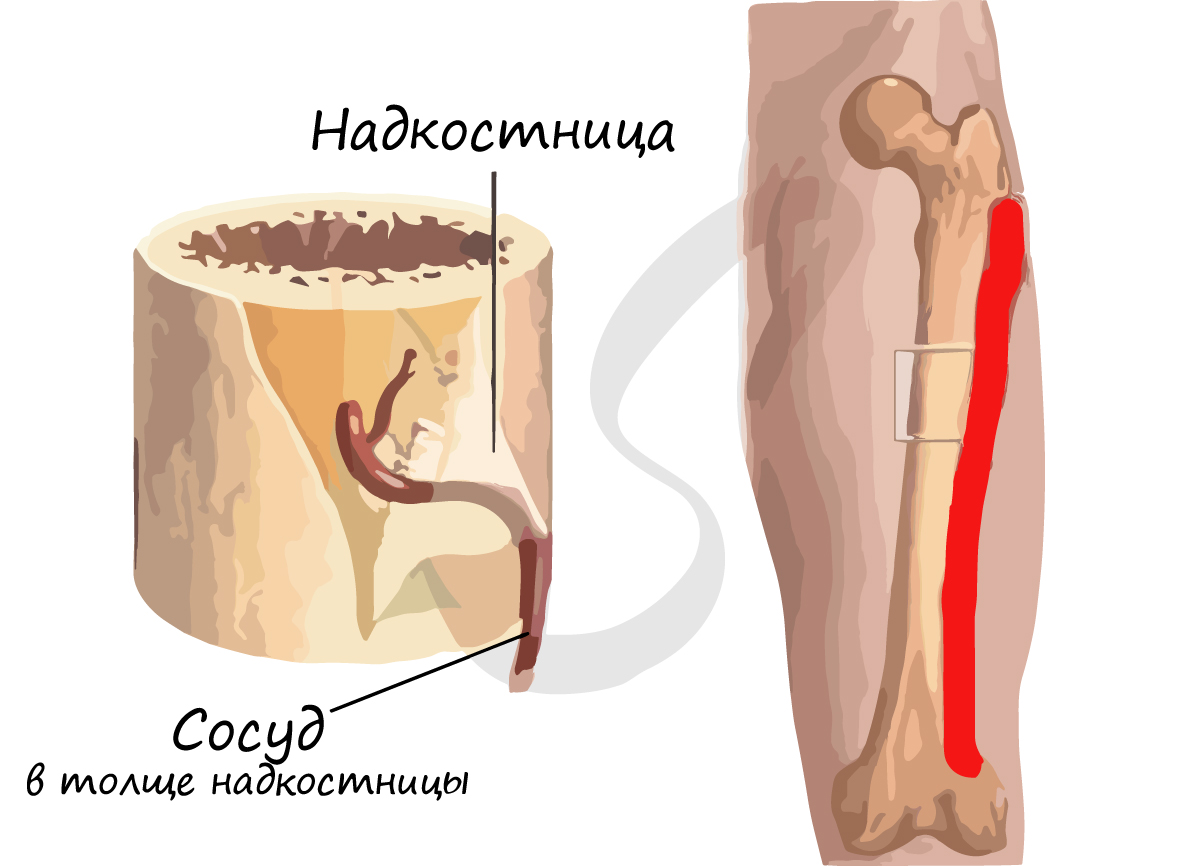

Кость состоит из костного вещества, костного мозга и надкостницы, а также имеет разветвленную сеть кровеносных сосудов и нервов, как показано на рисунке. Длинная бедренная кость состоит из диафиза и двух выпуклых эпифизарных концов. Поверхность каждого эпифизарного конца покрыта хрящом и образует гладкую суставную поверхность. Коэффициент трения в пространстве между хрящами в месте соединения сустава очень мал, он может быть ниже 0.0026. Это самый низкий известный показатель силы трения между твердыми телами, что позволяет хрящу и соседним костным тканям создать высокоэффективный сустав. Эпифизарная пластинка образована из кальцинированного хряща, соединенного с хрящом. Диафиз представляет собой полую кость, стенки которой образованы из плотной кости, которая является довольно толстой по всей ее длине и постепенно утончающейся к краям.

Надкостница представляет собой уплотненную соединительную ткань, тесно прилегающую к поверхности кости. Она содержит кровеносные сосуды и нервы, выполняющие питательную функцию. Внутри надкостницы находится большое количество остеобласта, обладающего высокой активностью, который в период роста и развития человека способен создавать кость и постепенно делать ее толще. Когда кость повреждается, остеобласт, находящийся в состоянии покоя внутри надкостницы, начинает активизироваться и превращается в костные клетки, что имеет важное значение для регенерации и восстановления кости.

Кольцевидные пластинки представляют собой пластинки, расположенные по окружности на внутренней и внешней стороне диафиза, и они подразделяются на внешние и внутренние кольцевидные пластинки. Внешние кольцевидные пластинки имеют от нескольких до более десятка слоев, они располагаются стройными рядами на внешней стороне диафиза, их поверхность покрыта надкостницей. Мелкие кровеносные сосуды в надкостнице пронизывают внешние кольцевидные пластинки и проникают вглубь костного вещества. Каналы для кровеносных сосудов, проходящие через внешние кольцевидные пластинки, называются фолькмановскими каналами (Volkmann’s Canal). Внутренние кольцевидные пластинки располагаются на поверхности костномозговой полости диафиза, они имеют небольшое количество слоев. Внутренние кольцевидные пластинки покрыты внутренней надкостницей, и через эти пластинки также проходят фолькмановские каналы, соединяющие мелкие кровеносные сосуды с сосудами костного мозга. Костные пластинки, концентрично расположенные между внутренними и внешними кольцевидными пластинками, называются гаверсовыми пластинками. Они имеют от нескольких до более десятка слоев, расположенных параллельно оси кости. В гаверсовых пластинках имеется один продольный маленький канал, называемый гаверсовым каналом, в котором находятся кровеносные сосуды, а также нервы и небольшое количество рыхлой соединительной ткани. Гаверсовы пластинки и гаверсовы каналы образуют гаверсову систему. Вследствие того, что в диафизе имеется большое число гаверсовых систем, эти системы называются остеонами (Osteon). Остеоны имеют цилиндрическую форму, их поверхность покрыта слоем цементина, в котором содержится большое количество неорганических составных частей кости, костного коллагенового волокна и крайне незначительное количество костного матрикса.

Внутрикостное кровообращение

В кости имеется система кровообращения, например, на рисунке показа модель кровообращения в плотной длинной кости. В диафизе есть главная питающая артерия и вены. В надкостнице нижней части кости имеется маленькое отверстие, через которое внутрь кости проходит питающая артерия. В костном мозге эта артерия разделяется на верхнюю и нижнюю ветви, каждая из которых в дальнейшем расходится на множество ответвлений, образующих на конечном участке капилляры, питающие ткани мозга и снабжающие питательными веществами плотную кость.

Кровеносные сосуды в конечной части эпифиза соединяются с питающей артерией, входящей в костномозговую полость эпифиза. Кровь в сосудах надкостницы поступает из нее наружу, средняя часть эпифиза в основном снабжается кровью из питающей артерии и лишь небольшое количество крови поступает в эпифиз из сосудов надкостницы. Если питающая артерия повреждается или перерезается при операции, то, возможно, что снабжение кровью эпифиза будет заменяться на питание из надкостницы, поскольку эти кровеносные сосуды взаимно связываются друг с другом при развитии плода.

Поверхность кости покрыта особой тканью, надкостницей, которая состоит из соединительной ткани и плотно сращена с подлежащей костной тканью. Именно за счёт надкостницы происходит рост кости в толщину, её регенерация в случае повреждений, питание кости за счёт широкой сети кровеносных сосудов, а также очищение через лимфатические сосуды. Именно в надкостнице заканчиваются чувствительные нервные окончания, в толще кости нервов нет. Костная ткань в связи со своей функцией имеет очень высокие показатели прочности, так, например, сопротивление на разрыв такое же, как у меди, и в 9 раз больше, чем у свинца. Предельная нагрузка на сжатие близка к показателю чугуна.